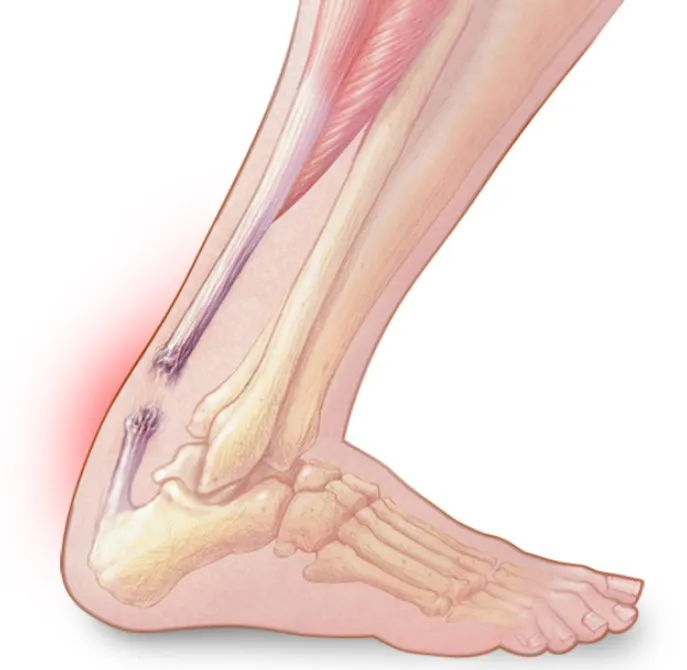

2. 跟腱炎或断裂

跟腱是体内最大的肌腱。它位于腿部的后侧,将小腿肌肉连接到跟骨。

当肌腱受到刺激时,通常是由于过度使用,可能会出现以下跟腱炎症状:

腿后部脚后跟上方有灼痛

小腿疼痛和僵硬

肌腱撕裂被称为跟腱断裂。当肌腱撕裂时,可能会出现:

腿后部突然剧烈疼痛

受伤时听到“砰”的一声

腿部难以负重

跟腱撕裂。右踝关节侧位X线片显示跟骨附着物撕脱(箭头),表明退行性跟腱撕裂;Kager脂肪垫内异常密度(*),表明相关的跟骨后滑囊炎。MRI帮助确认跟腱撕裂,有2厘米的间隙。手术修复时证实肌腱完全断裂。这个病例说明了使用Kager脂肪垫对踝关节疾病的影像学诊断的重要性。